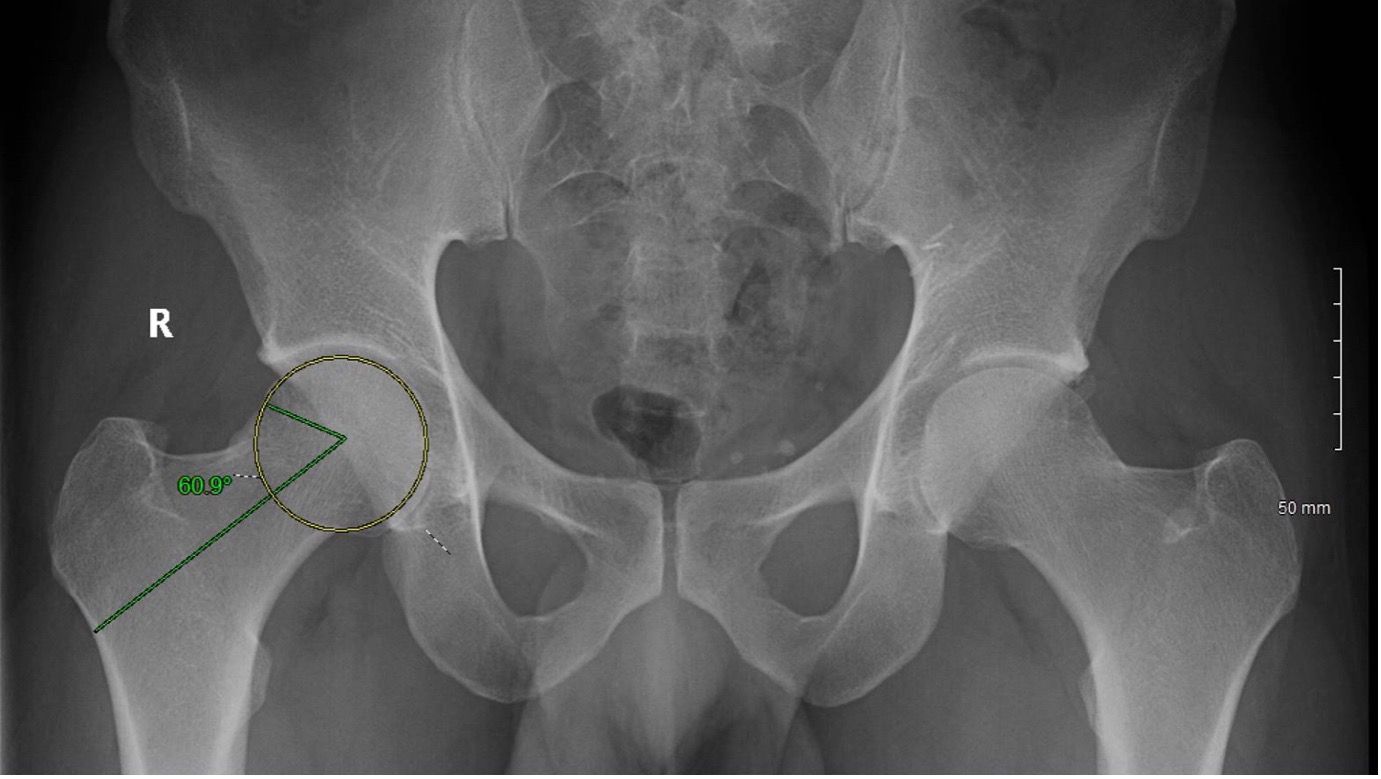

Radiologically, FAI is assessed with an anterior-posterior (AP) pelvis, and a cross table lateral hip radiograph. Besides the aforementioned morphological abnormalities, the asphericity of the femoral head neck junction and the crossover sign with the ischial spine sign indicate cam and pincer impingement respectively [12]. A Dunn view radiograph (taken in supine position with ipsilateral hip in 90° flexion and 20° abduction) is very sensitive to identify subtle cam deformities [13]. Alternatively, a frog-leg lateral radiograph can also be used to calculate the alpha angle to diagnose a cam type deformity [12]. The alpha angle is measured between one line intersecting the centre of the femoral neck and head, and another line intersecting the centre of the femoral head and the beginning of the prominence of the head-neck junction [6]. An alpha angle greater than 50 degrees indicates a cam type deformity (see Figures 1 and 2) [6].